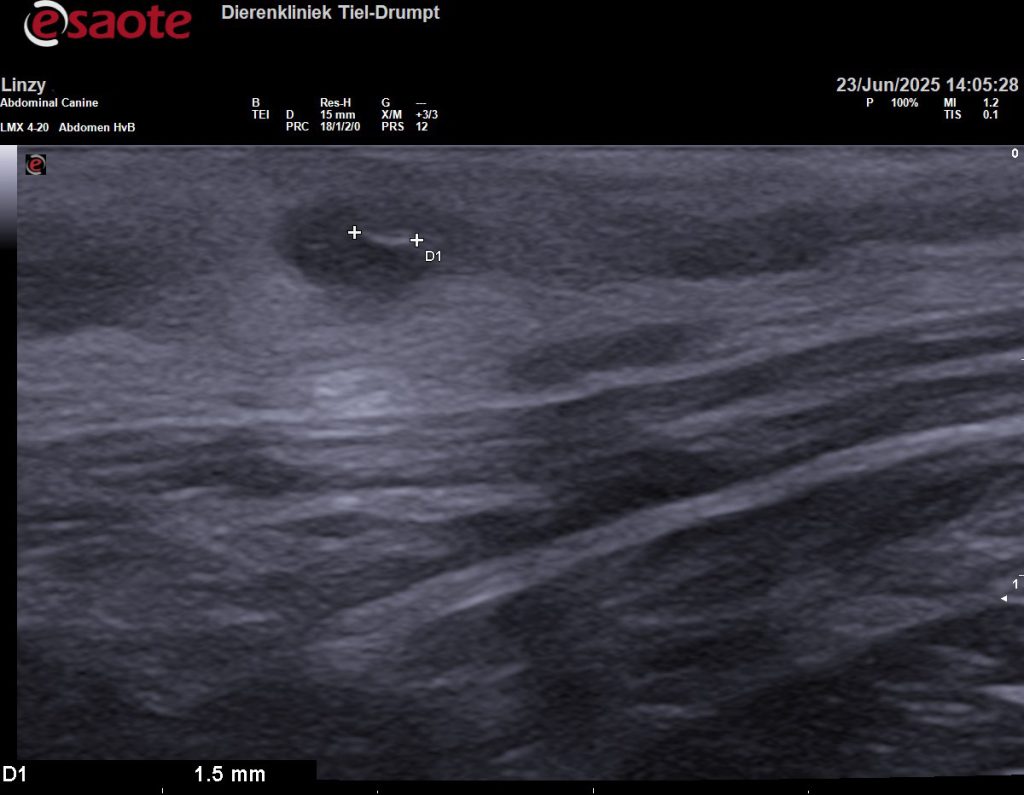

Om meer duidelijkheid te hebben, om te voorkomen dat we voor niks chirurgisch zouden ingrijpen, hebben we de plek eerst bekeken met een echo. Gelukkig hebben we ook een echokop voor zeer veel detail en het beeld bleek eigenlijk heel goed bij een grasaar te passen.

Om zeker te weten dat we alles hadden is het weefsel geopend, voordat we de wond gingen sluiten. In eerste instantie leek het alsof er geen grasaar in het weefsel zat. Maar dit liet maar weer zien hoeveel ons echoapparaat kan vergroten, want op de echobeelden is de diameter van de grasaar 1,5 millimeter en 12,4 millimeter lang. Na een paar sneden vonden we het steekkanaal en de daadwerkelijke grasaar.